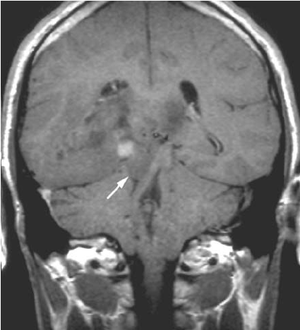

Diagnosis?

Uncal herniation!